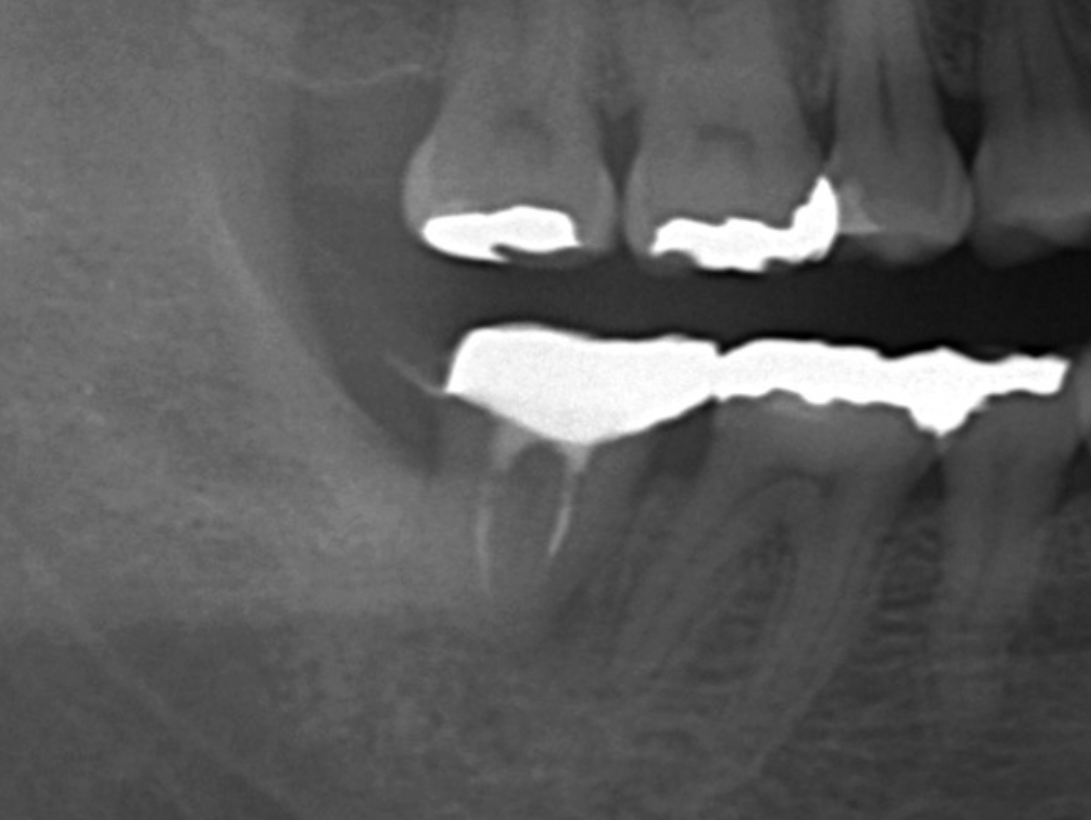

- 충치 제거 및 신경치료 여부 확인

- 치아 삭제 및 크라운 공간 확보

- 치아 본뜨기 또는 디지털 스캔

최근에는 디지털 스캔 장비를 사용해 치아 본을 뜨는 과정이 더 정밀해졌습니다. 이러한 기술 덕분에 크라운의 정확도와 적합도가 크게 향상되었습니다.